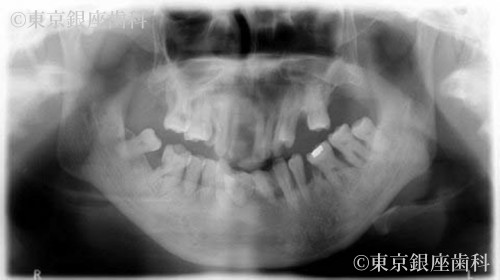

Before

重度歯周病と口臭に悩み、抜歯とインプラントで清掃性が改善。口臭も消失し前向きな生活に変化。最終補綴まで約1年半。